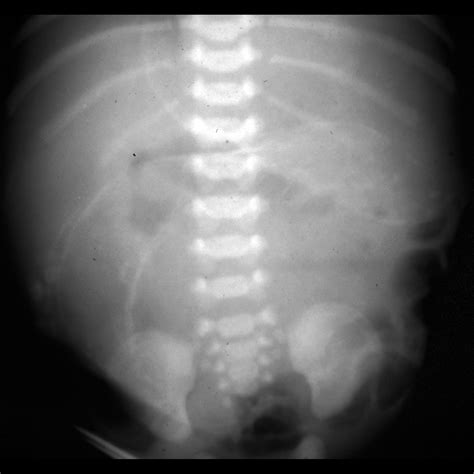

• Imaging Tests: In some cases, imaging tests such as X-rays or ultrasounds may be ordered to visualize the intestines and identify any blockages or abnormalities.